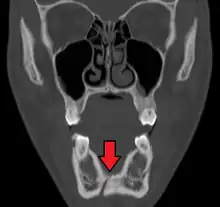

Computed tomography

Computed tomography is the most sensitive and specific of the imaging techniques. The facial bones can be visualized as slices through the skeletal in either the axial, coronal or sagittal planes. Images can be reconstructed into a 3-dimensional view, to give a better sense of the displacement of various fragments. 3D reconstruction, however, can mask smaller fractures owing to volume averaging, scatter artifact and surrounding structures simply blocking the view of underlying areas.